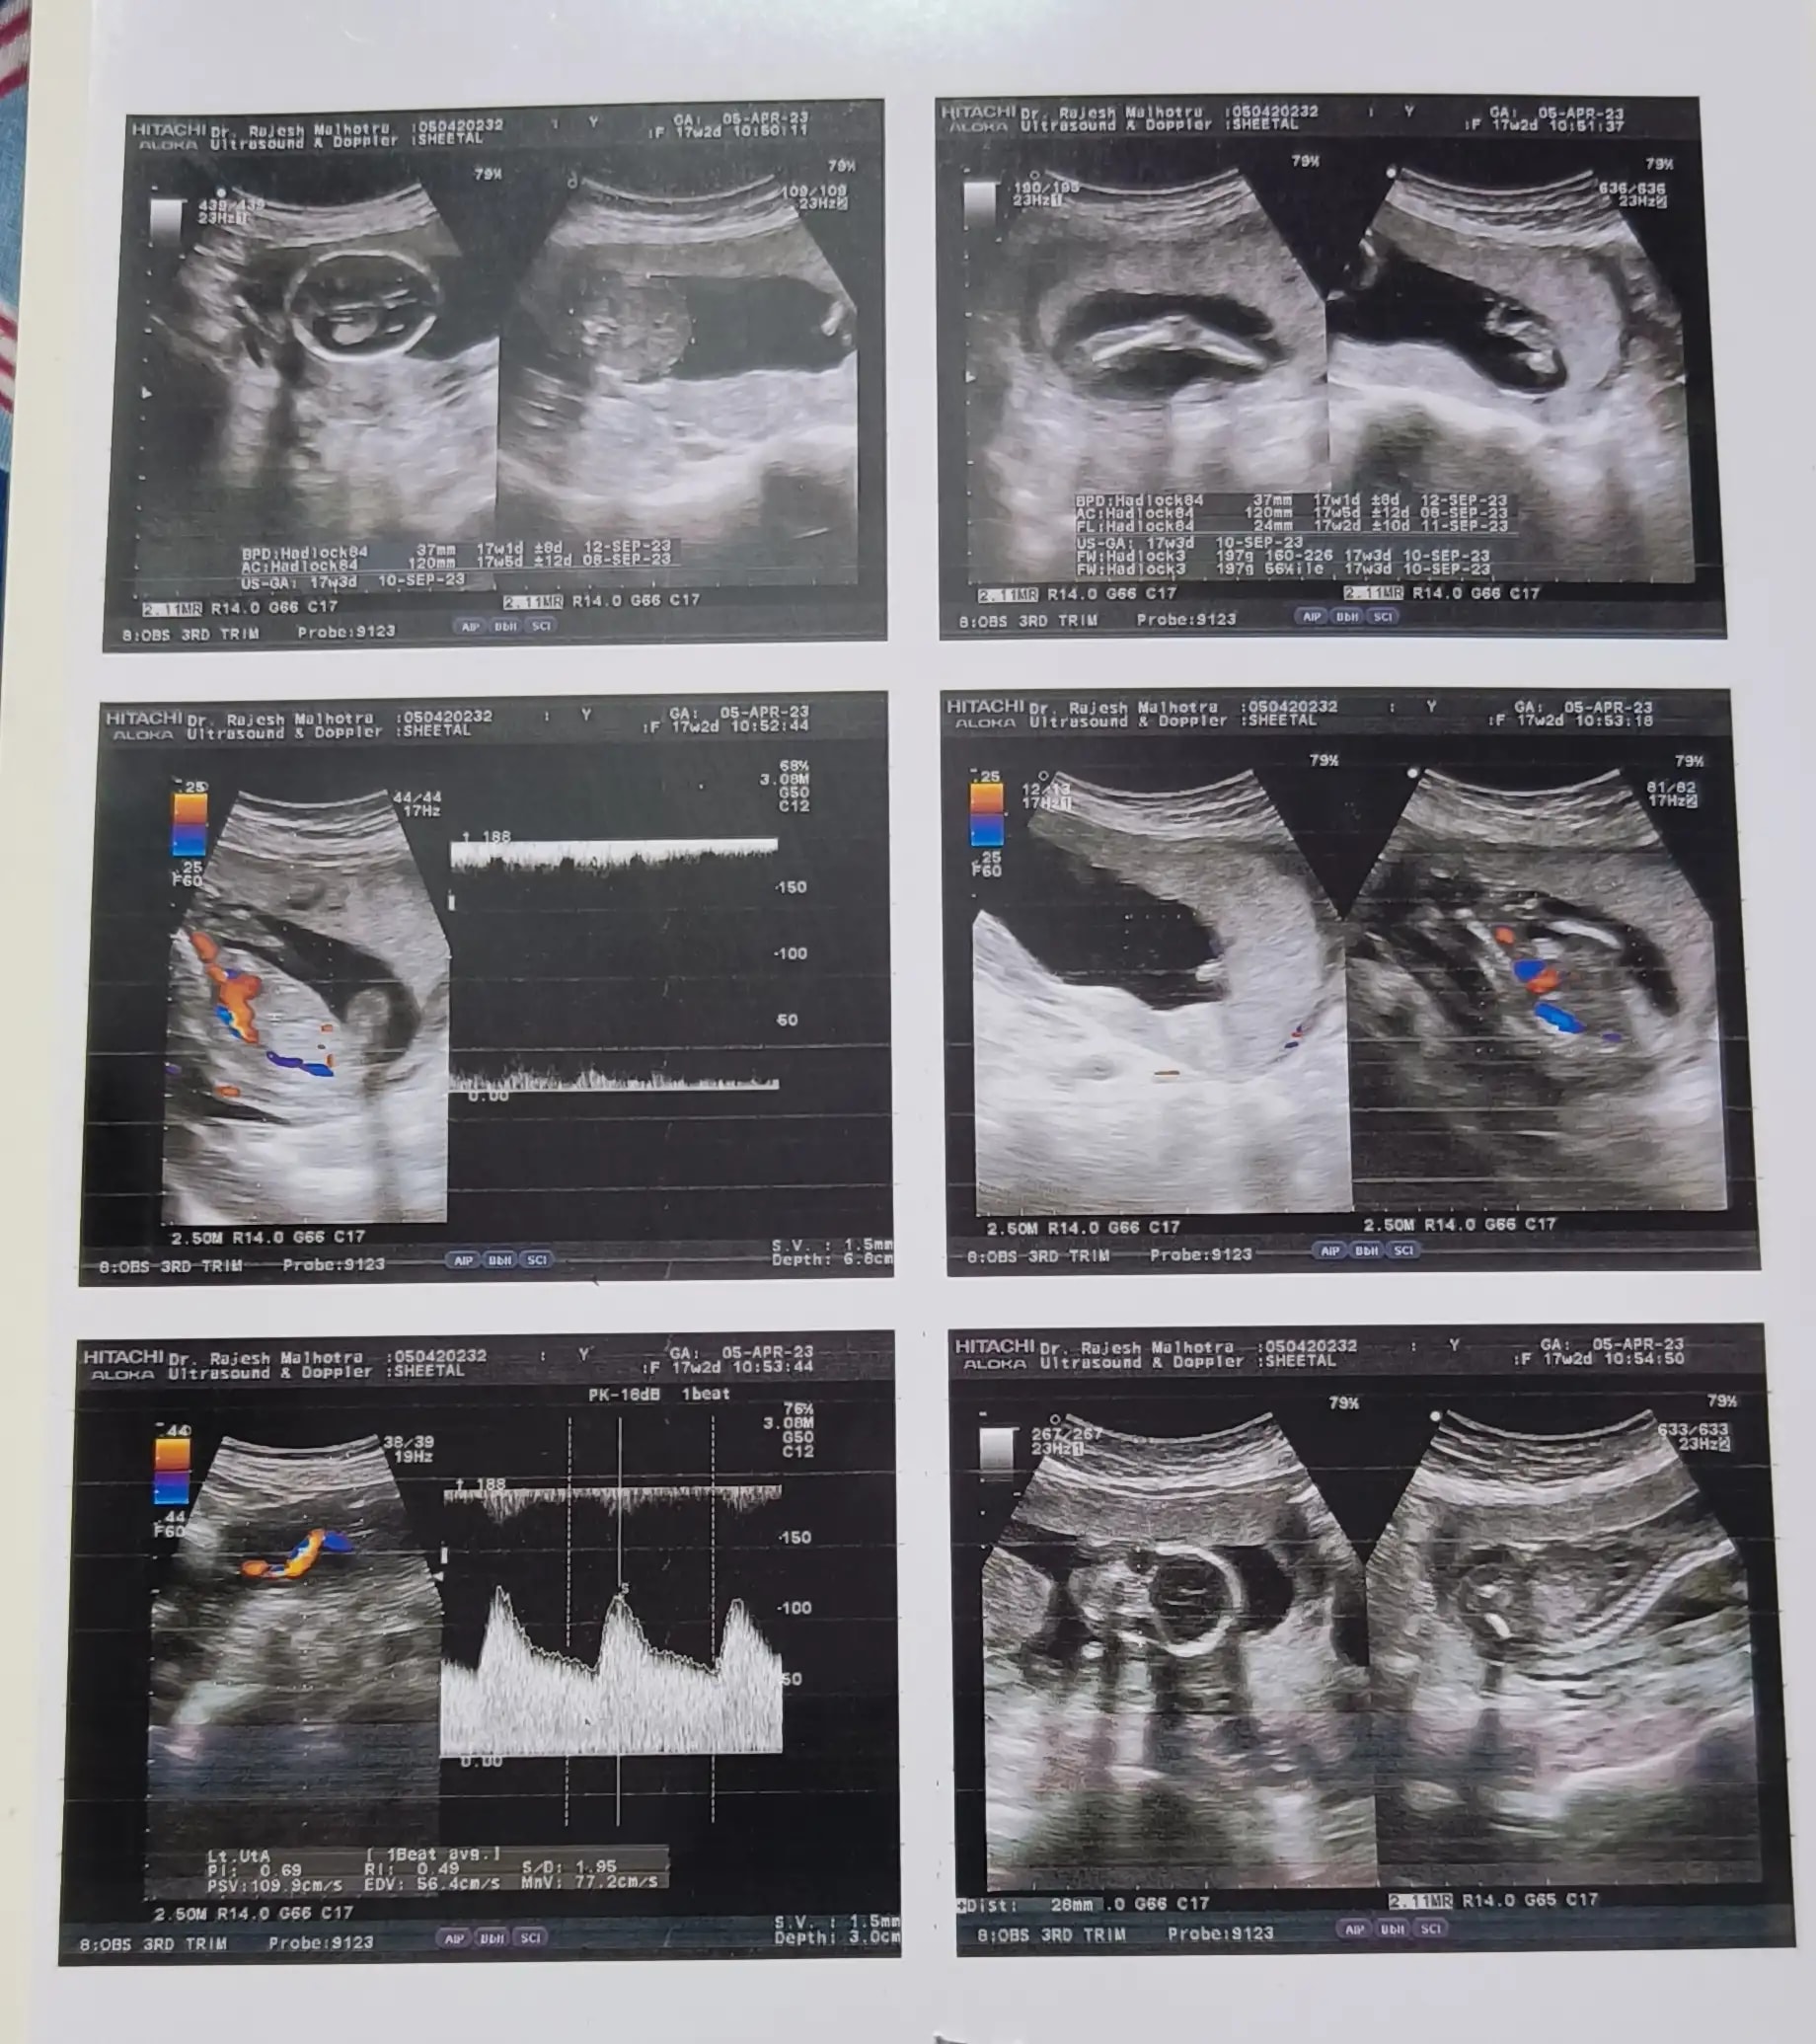

Q: Ye meri level 2 ultrasound report hai dekhna mujhe kiya hoga mere phle se ek beti h usko bhai chahiye dekhna mujhe kiya hoga plzz help me.

• Ye meri level 2 ultrasound ki report hai dekhna sab theek hai ya kuch Kami hai report m phle beti h mere par ab dekhna kiya hoga . Plzz javab jarur den.